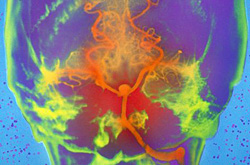

Внутримозговое кровоизлияние относят к острым нарушениям мозгового кровообращения (ОНМК) по геморрагическому типу. Любые внутримозговые кровоизлияния обычно развиваются остро, с непрерывным нарастанием симптоматики в течение нескольких минут или часов.

Причины кровоизлияния: В 70-80% случаев спонтанное кровоизлияние в мозг это следствие артериальной гипертензии; более редкие причины: аневризмы и мальформации, опухоли мозга, антикоагулянтная терапия, тромбозы мозговых вен и венозных синусов, септические эмболии, мигрень, кровоизлияние при физическом напряжении, при жировой эмболии, кровоизлияние при острой интенсивной боли и др.

По причине развития заболевания различают: первичные кровоизлияния в мозг (связаны чаще всего с артериальной гипертензией); вторичные кровоизлияния в мозг (связано с патологией сосудов: аневризмы, мальформации, васкулиты и др.);